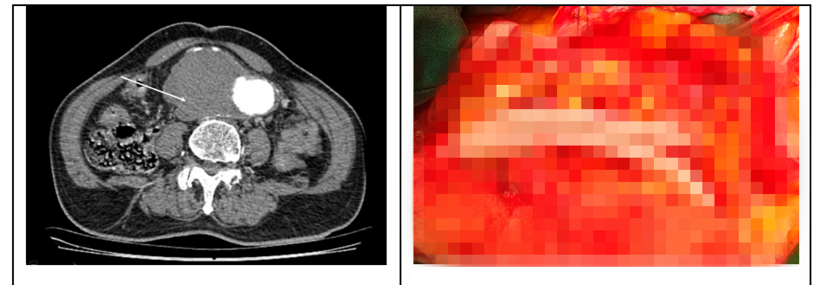

Chụp cắt lớp vi tính phát hiện khối phình rất lớn động mạch chủ bụng dưới thận đường kính gần 9cm trên đoạn dài đến tận động mạch chậu gốc hai bên và có dấu hiệu vỡ, kèm theo thấy dày thành đại tràng sigma trực tràng thâm nhiễm ra xung quanh vào động mạch chậu hai bên.

Hình ảnh khối phồng động mạch chủ lớn doạ vỡ trên Chụp CLVT (trái) và hình ảnh mạch máu nhân tạo được thay vào chỗ đoạn mạch phình cắt bỏ. Ảnh: BVCC

Cuộc phẫu thuật kéo dài gần 5h, các bác sĩ đã thực hiện ghép đoạn động mạch chủ bụng động mạch chậu hai bên bằng đoạn mạch nhân tạo; cắt đoạn đại trực tràng có u và nối ngay. Sau mổ tình trạng huyết động ổn định, các chỉ số xét nghiệm máu trong giới hạn bình thường, trung tiện sau 3 ngày. Sau 11 ngày bệnh nhân đã đi lại và ăn uống bình thường, động mạch ghép lưu thông tốt, không có dấu hiệu thiếu máu chi dưới, bệnh nhân đi đại tiện bình thường, kết quả giải phẫu bệnh là ung thư đại tràng.